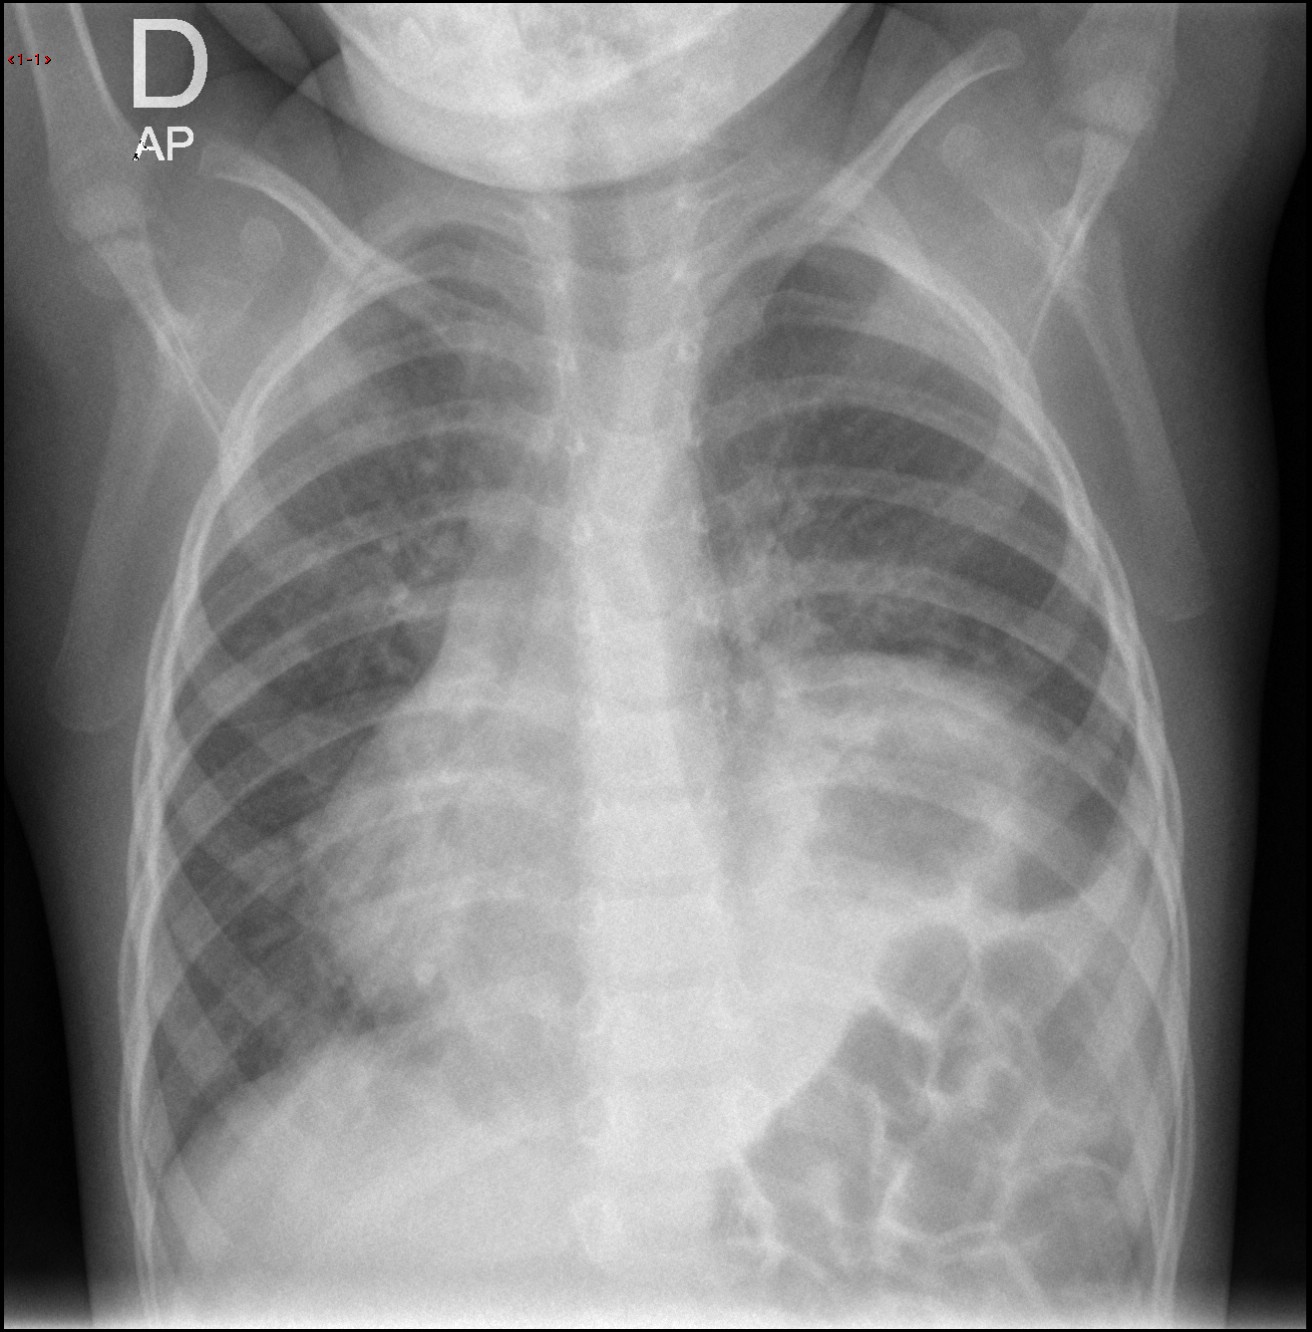

Usted ha decidido realizar una radiografía de tórax.

Ya con la paciente de nuevo en Urgencias, consulta la imagen en el ordenador…

El radiólogo le dice que está informando una tomografía computarizada y le resulta imposible informar su radiografía. ¿Qué puede ver en la imagen?